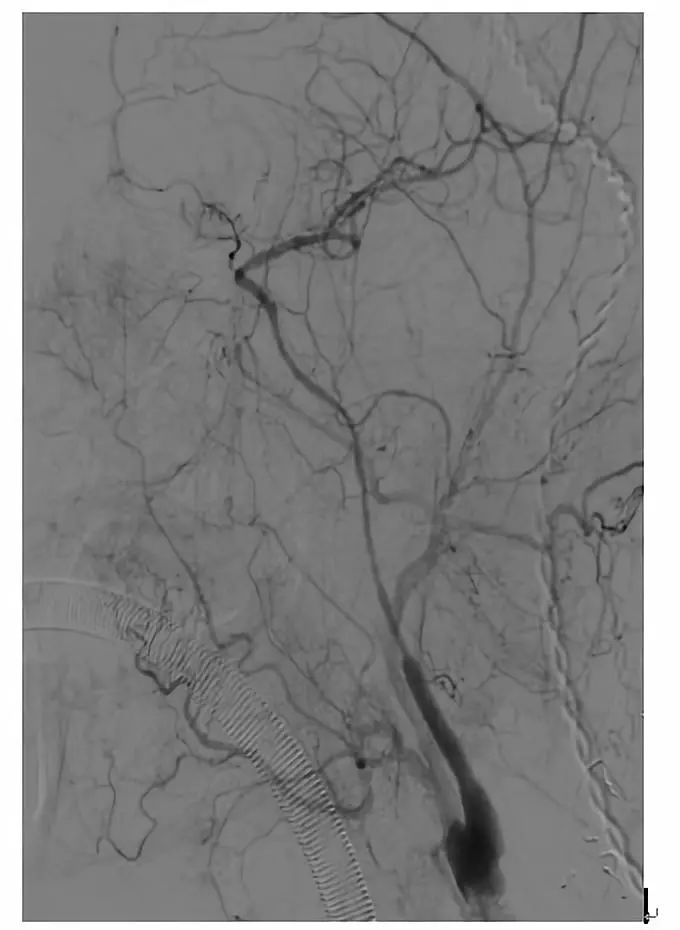

术前造影显示颈动脉C1-C4闭塞

颈动脉内膜剥脱后可见闭塞处血流缓慢。

近端闭塞处置入支架后,可见海绵窦段极重度狭窄

术中用小球囊2.5-20mm的球囊扩张海绵窦段狭窄处。

球囊扩张后,海绵窦段血流通畅。